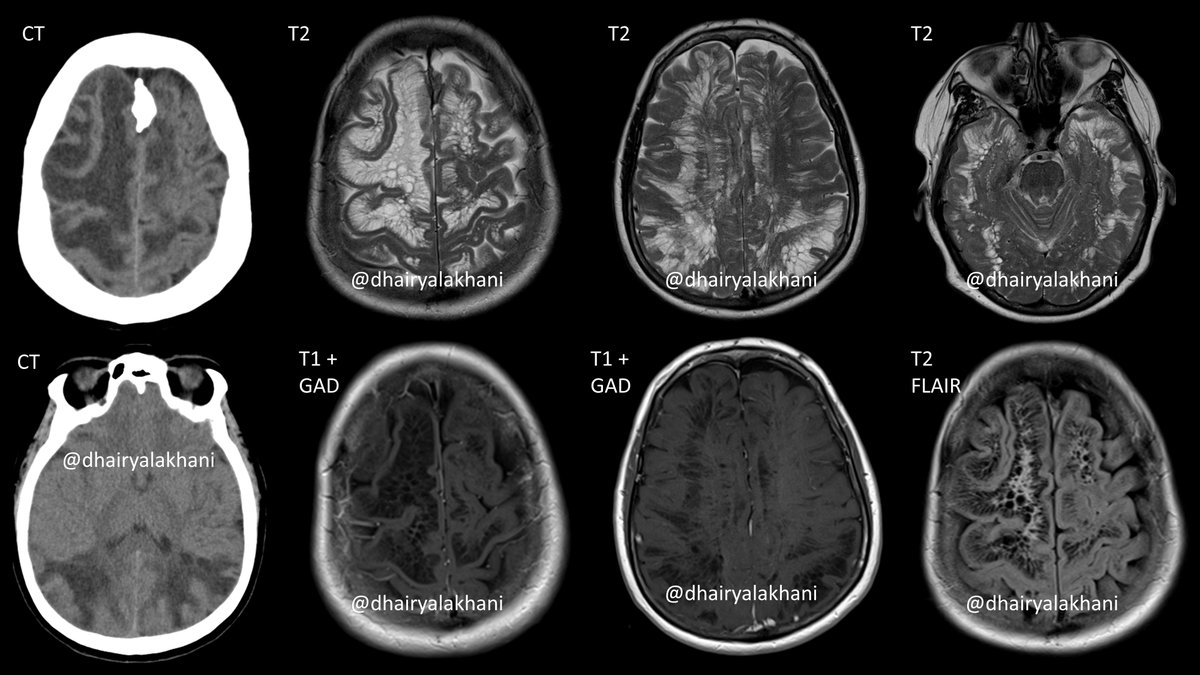

Middle-aged woman presents w trauma ✅CT: No bleed, diffuse WM changes ✅MR: Innumerable cystic foci extending to subcortical WM. Slight increased peri-lesional FLAIR signal. No enhancement. GM is stretched & displaced ✅Diagnosis: Giant Tumefactive Perivascular Spaces #RadRes

Middle-aged woman presents w trauma

✅CT: No bleed, diffuse WM changes

✅MR: Innumerable cystic foci extending to subcortical WM. Slight increased peri-lesional FLAIR signal. No enhancement. GM is stretched &amp; displaced

✅Diagnosis: Giant Tumefactive Perivascular Spaces

#RadRes